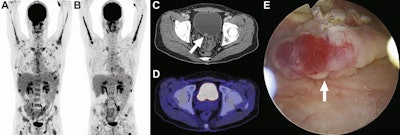

A 40-year-old man with plasmablastic lymphoma and multiple bone lesions underwent FDG-PET at baseline (A) and six months later (B). CT shows a focal hyperdense lesion at the bladder floor (C, arrow) that is not clearly visible on fused FDG-PET/CT (D). The FDG-PET/CT report included a strong recommendation for focused ultrasonography to evaluate the bladder lesion. However, the referring physician disregarded the recommendation for unclear reasons. Six months later, the patient presented with hematuria, and cystoscopy showed a bladder tumor, which was removed by transurethral resection (E, arrow). Images courtesy of JACR.A 40-year-old man with plasmablastic lymphoma and multiple bone lesions underwent FDG-PET at baseline (A) and six months later (B). CT shows a focal hyperdense lesion at the bladder floor (C, arrow) that is not clearly visible on fused FDG-PET/CT (D). The FDG-PET/CT report included a strong recommendation for focused ultrasonography to evaluate the bladder lesion. However, the referring physician disregarded the recommendation for unclear reasons. Six months later, the patient presented with hematuria, and cystoscopy showed a bladder tumor, which was removed by transurethral resection (E, arrow). Images courtesy of JACR.